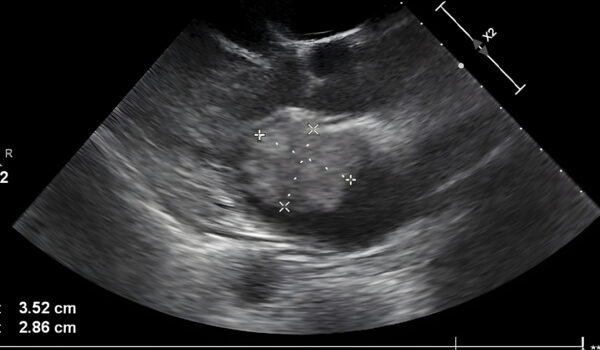

During the appointment, Bailey noticed something unusual in the ultrasound image. She asked her mother whose hand appeared to be cradling the baby’s head, prompting Amanda to examine the image closely herself with a mixture of shock and awe.

Amanda shared the image on Facebook, describing it as showing the divine presence of a hand gently holding her son’s head. She expressed profound gratitude for what she perceived as God’s protective touch over Kyler.

In her post, Amanda wrote, “In one of his pictures it has the appearance of a hand holding his head,” adding that the sight brought her to tears, reflecting on all God has done for her family.

Medical professionals caution that while unusual shapes may appear in ultrasound images, Amanda’s interpretation is a personal and meaningful reflection of her faith and emotional journey throughout pregnancy.